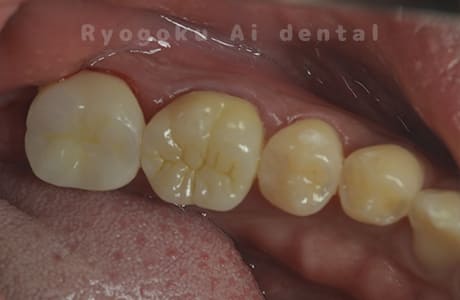

Case11

- 治療内容

- セラミッククラウン、セラミックインレー

- 治療費用

- 123,000円×2(セラミッククラン)、77,000円(セラミックインレー)

銀歯が取れて、ご来院された患者様です。奥歯2本をセラミッククラウン、手前の小臼歯をセラミックインレーで治療を行いました。